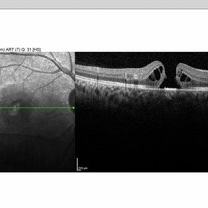

Full Thickness Macular Hole OCT

OCT of an 14 years old man with Full Thickness Macular Hole after direct exposure of the blue laser to his eye

Photographer: Tareq alsulami ophthalmic technician-king Abdullah Medical City-Saudi Arabia

Imaging device: Heidelberg